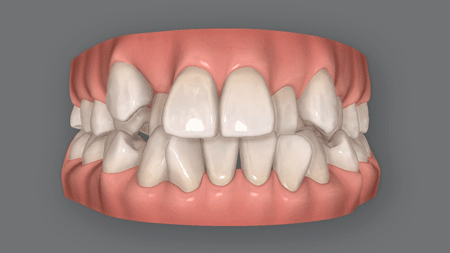

上下顎前突(じょうげがくぜんとつ)とも呼ばれる口ゴボは、上下の前歯が前方に飛び出して見える症状。

また歯がガタガタの叢生乱杭歯)や、八重歯を併発している患者さんも少なくありませんが、こうした症状も口ゴボの矯正で治せます。

先ほどご説明した通り、小顔で顎が小さい方はスペースが足りません。そこでスペースを確保するために、前歯しか動かせない格安矯正でよく用いられるのが、拡大床という治療法です。

ネジの力を利用して歯を外側へ押し広げることで、前歯を並べるスペースを確保します。

ただ拡大床は、歯列を広げすぎないよう細心の注意を払う必要がある、とても難しい治療法

経験不足の歯科医師では、過度に歯を押し広げてしまい、口ゴボかえって酷くなることがあります。